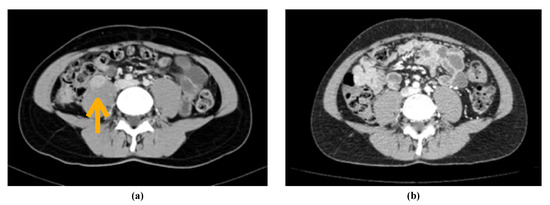

2. Case Report